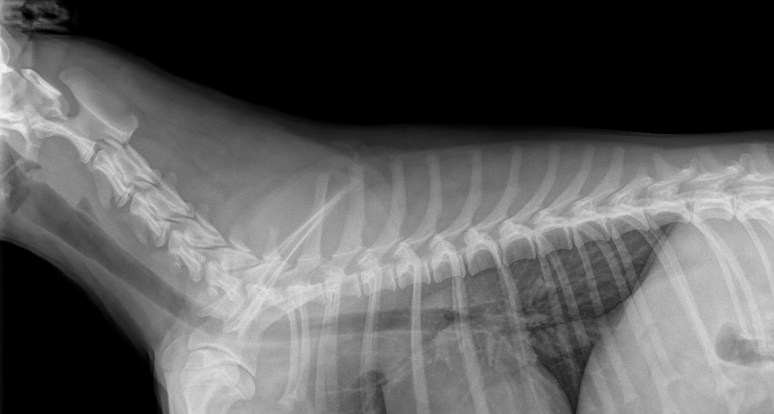

Voici d’ailleurs une radiographie prise quelques minutes plus tard sans la muselière:

La première chose que l’on apprend comme résident en imagerie est de toujours s’assurer que la lésion est 1) réelle (pas une image construite) et 2) qu’elle se situe bien dans le chien (ou le chat, le cheval, le veau, le cochon, etc.), un principe qui s’applique parfaitement dans ce cas-ci.